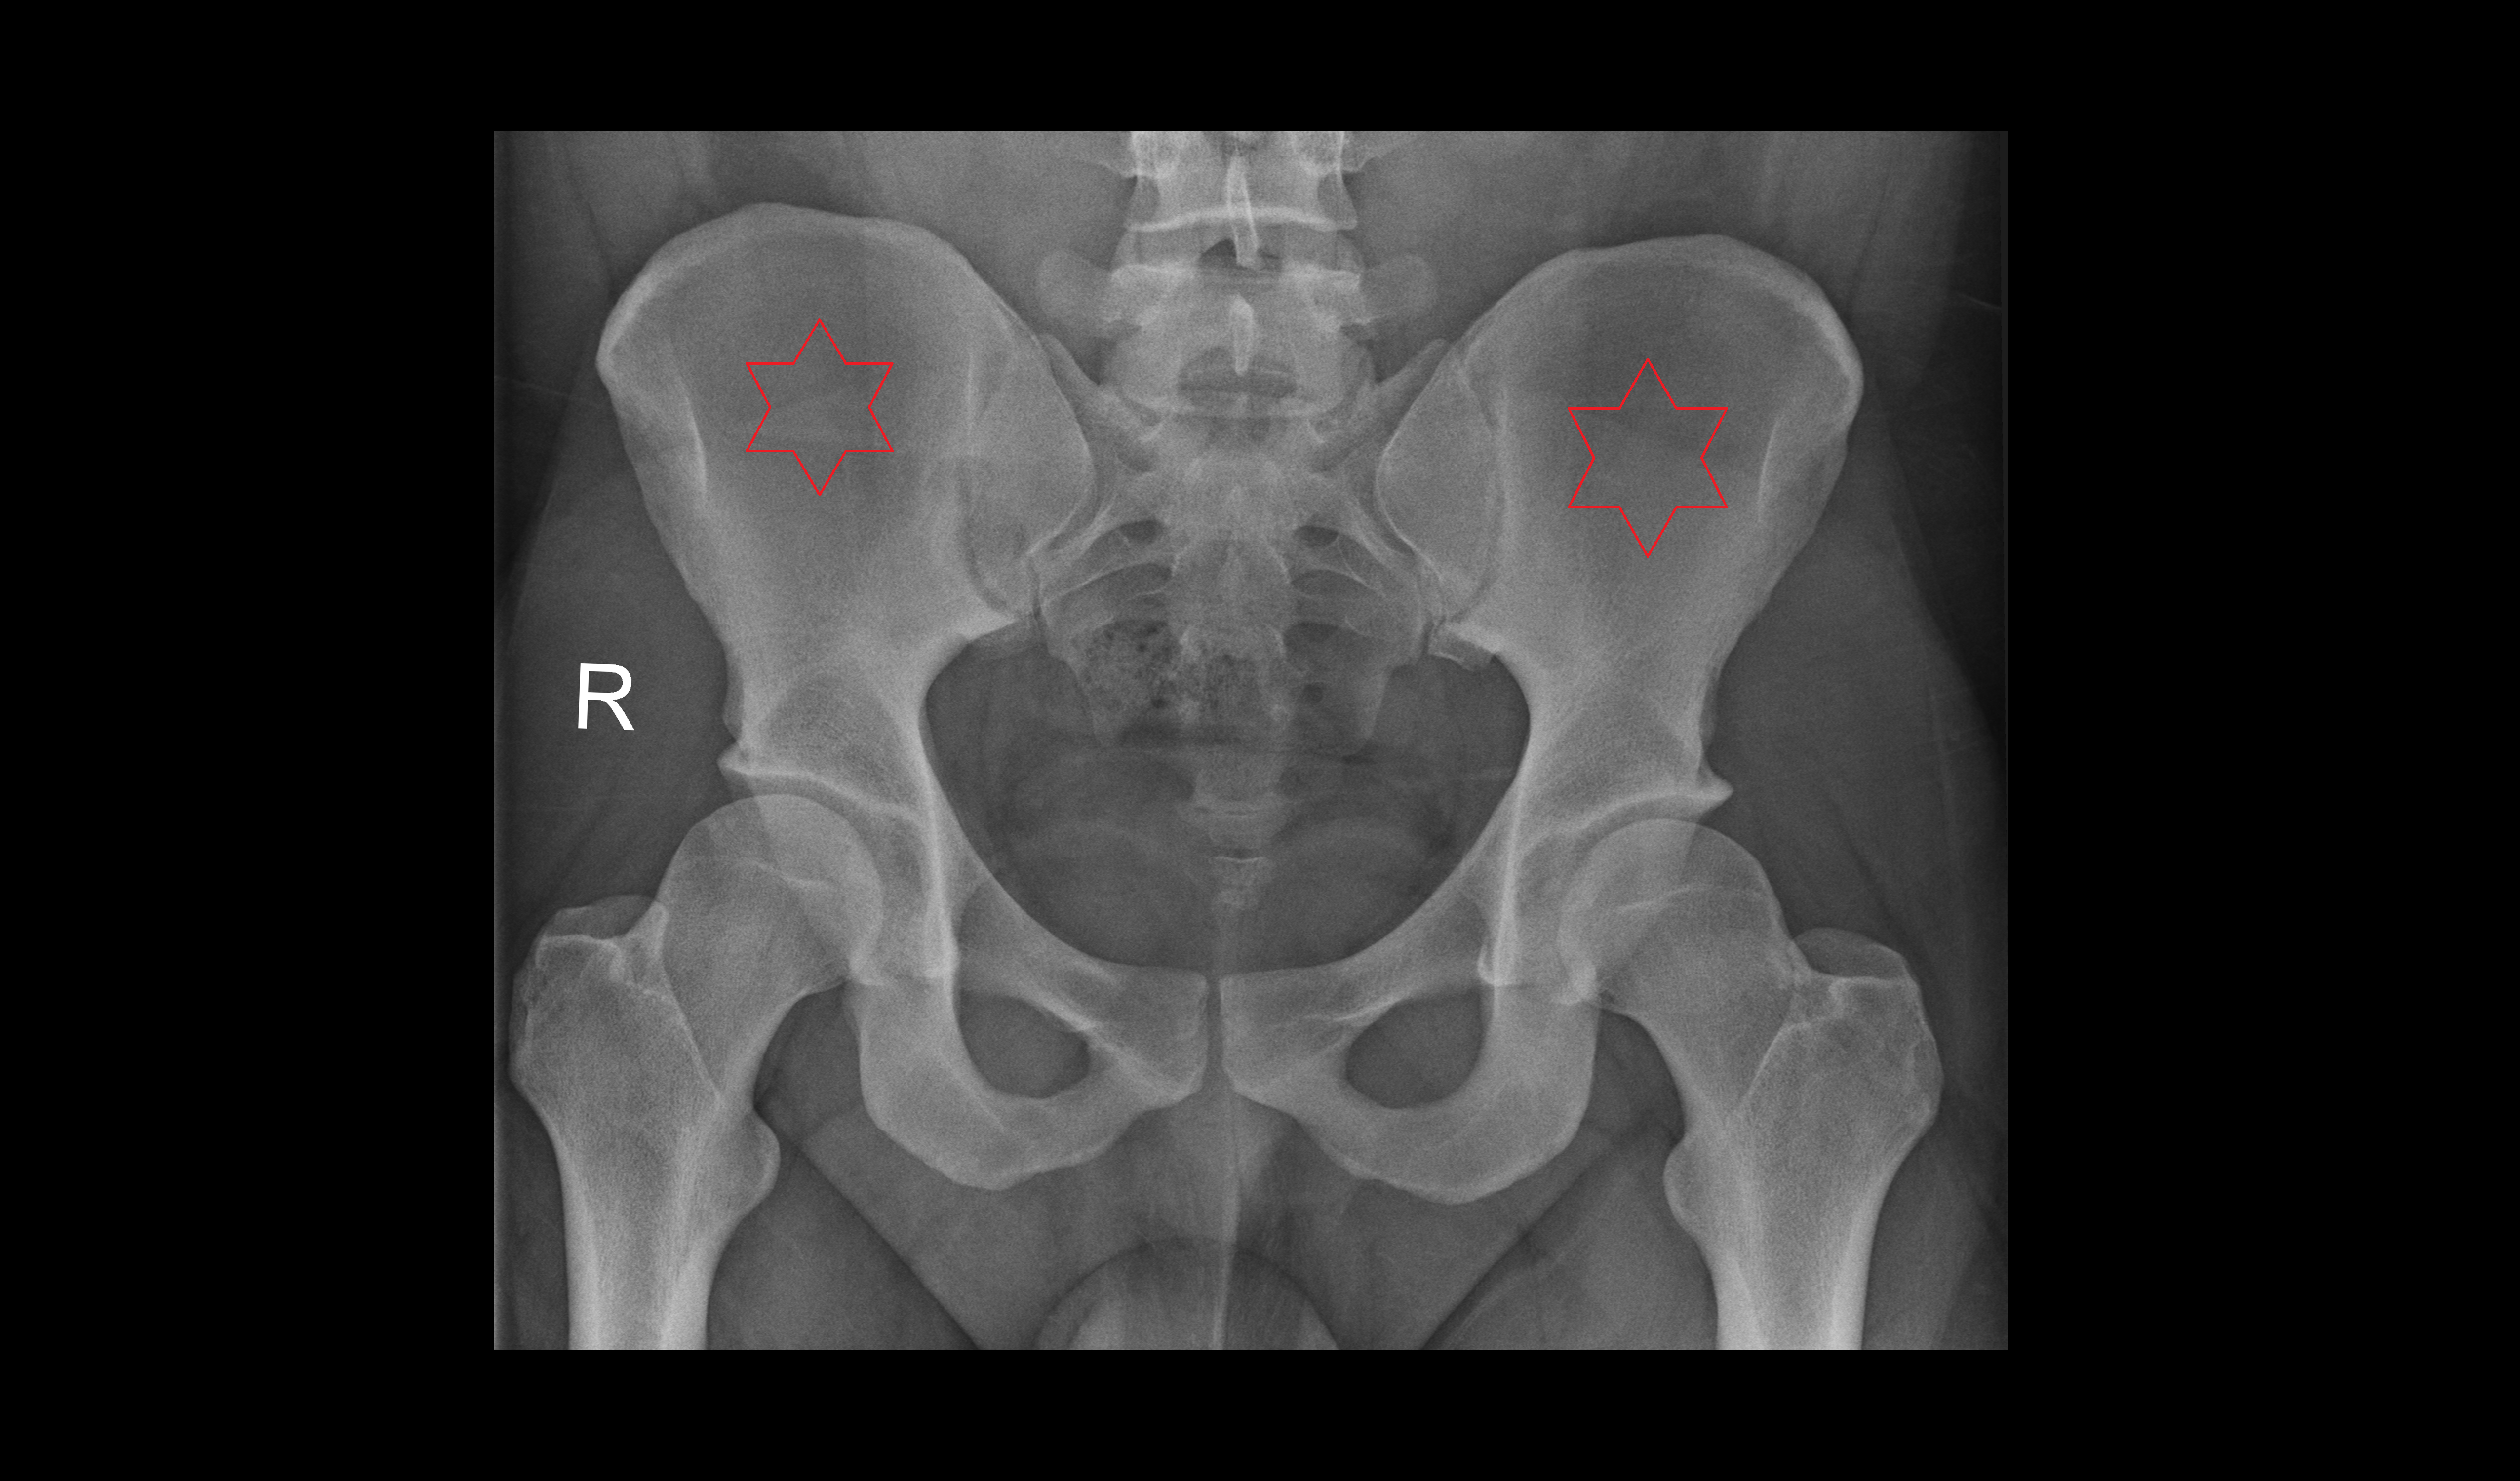

- Acetabulum

- Ilium bone

- Ischium bone

- Pubic bone

- Head of femur

- Neck of femur

- Greater trochanter

- Lesser trochanter

- Ala of ilium (wing of ilium)

- Iliac crest

- Sacrum

- Sacroiliac joint

- Pubic symphysis